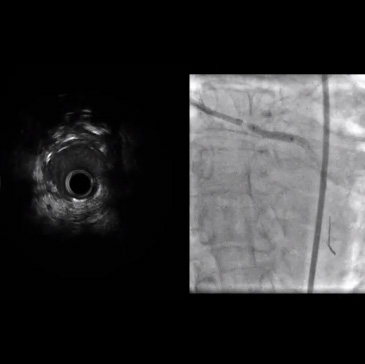

Barrido IVUS posterior a DES

• A continuación, se utilizó ROTABLATOR con una oliva ROTABLATOR de 2,0 mm.

• La lesión fue evaluada y predilatada a alta presión con un balón NC QUANTUM APEX de 3,25 x 15 mm.

• Se implantó un stent DES de 3,5 x 16 mm con una expansión excelente guiada por fluoroscopia.

• La ecografía intravascular post-stent

• La posdilatación se realizó a alta presión con un balón NC QUANTUM APEX de 3,75 x 12 mm.

• La angiografía final mostró flujo de TIMI-3, sin disecciones y sin estenosis residual en la arteria circunfleja.